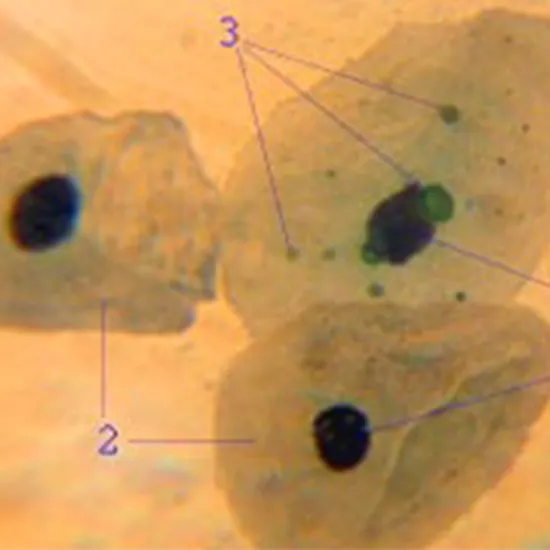

Chlamydia pneumoniae is a bacterium that infects humans and causes respiratory distress in the elderly and sick. Most Chlamydia pneumoniae infections cause minor illnesses such as sore throats, sinus infections, or respiratory tract infections. Infection with this bacterium may cause lower respiratory infections such as bronchitis, pneumonia, and others in some cases.

Now, the Chlamydia pneumoniae is classically considered as the Gram-negative, because it would not be able to retain the crystal violet dye along with gram staining. Additionally, it would have an outer lipopolysaccharide membrane which all the Gram-negative bacteria also have.